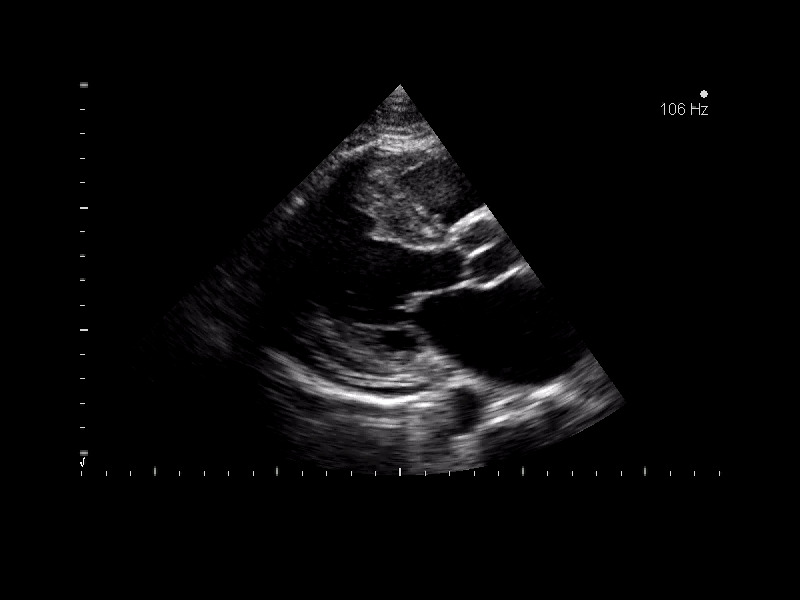

Miocardio non-compattato del ventricolo destro

Autore:

Andrea Barbieri